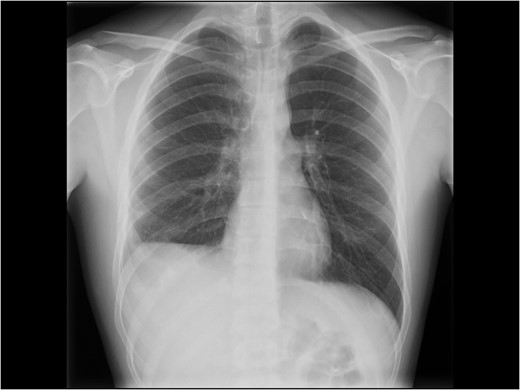

Chest X-ray at follow-up. Still some degree of diaphragm high-stand on the right side.